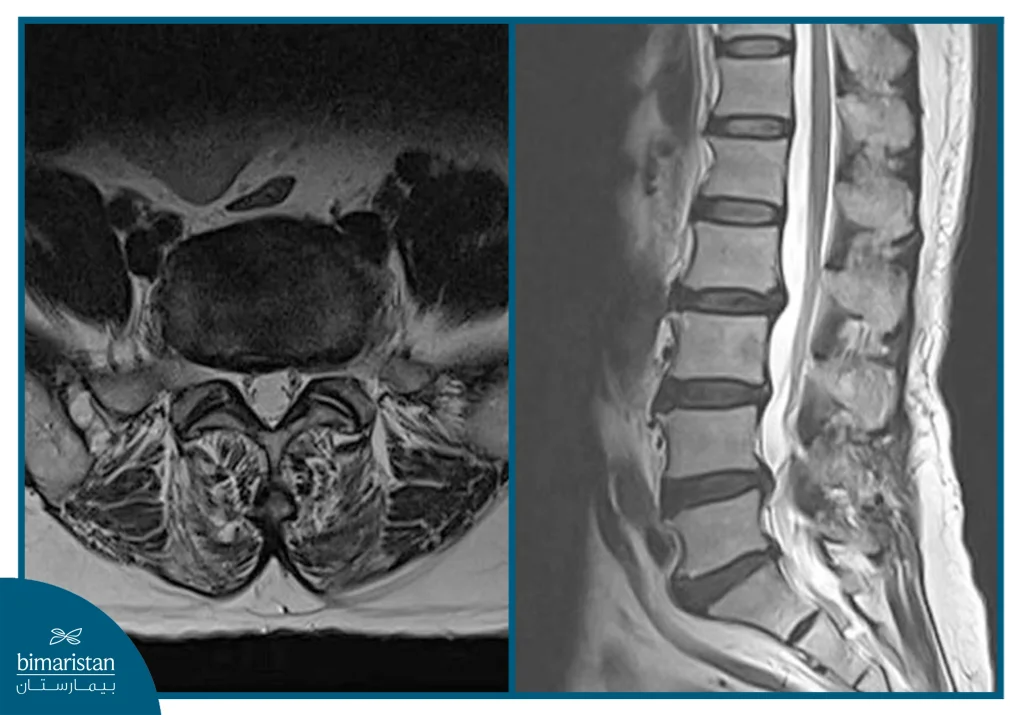

إن معنى أنواع الانزلاق الغضروفي حسب الشكل يعني حسب ما تُظهره صورة الرنين المغناطيسي (MRI)، حيث أنها تُظهر تفاصيلاً دقيقة تسمح للطبيب بتمييز أنواع الديسك من حيث شكل الانزلاق ودرجة التضرر الواقع على الغضروف والأعصاب المجاورة، ويمكن تصنيف الانزلاق الغضروفي إلى ثلاثة أشكال رئيسية تختلف من حيث شدة الحالة والخيارات العلاجية المناسبة.

في هذا النوع تنفصل قطعة من المادة الغضروفية بشكل كامل داخل القناة الشوكية، فتسبب ضغطاً مباشراً على الجذور العصبية، ويُعد هذا الشكل من أخطر أنواع الديسك، ويُشخّص عادةً بواسطة الرنين المغناطيسي بدقة عالية، وغالباً يحتاج إلى علاج جراحي عاجل لتفادي المضاعفات العصبية المستقبلية.

يُعتبر التصوير بالرنين المغناطيسي (MRI) الوسيلة الأهم لتشخيص أنواع الديسك والتفريق بينها، إذ يوضّح حالة الغضروف بدقة، وموقع الضغط العصبي الحاصل، ومدى تضرر الأنسجة المحيطة، ولكن في بعض الحالات قد يتطلب الأمر إجراء تصوير طبقي محوري (CT)، أو عمل تخطيط للأعصاب (EMG)، وذلك للمساعدة في تحديد درجة تهّيج الأعصاب أو استبعاد أمراض أخرى قد تسبب أعراضاً مشابهة.